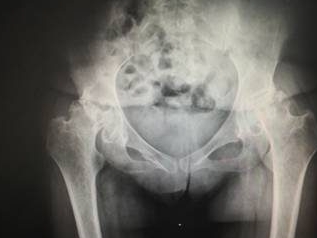

髋关节是人体负重的“核心枢纽”,而股骨头坏死作为中老年人高发…… 【详情】

股骨头坏死前期,骨骼尚未严重塌陷,但髋部疼痛、活动受限等症状已悄…… 【详情】